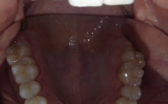

- Before

- During